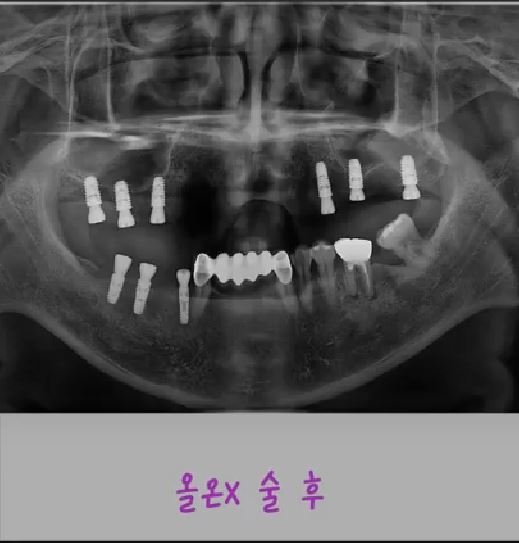

제목 뼈이식 최소한으로 빠르게 가능한 풀아치 임플란트, 올온X(All-on-X) 시술 안내

Emotion Icon올온X(All-on-X)란?

올온X는 소수의 임플란트를 전략적으로 식립하여

위 또는 아래 전체 치아를 한 번에 회복하는 풀아치 임플란트 치료법입니다.

기존 방식처럼 치아 하나하나를 심는 것이 아니라,

각도가 조절된 임플란트를 좋은 뼈에 선택적으로 식립하여

적은 개수의 임플란트로 전체 보철을 안정적으로 지지합니다.

저희 병원은

디지털 진단 시스템을 기반으로

좋은 뼈에 정확히 식립하여 뼈이식을 최소화하고,

빠른 보철 완성을 목표로 하는 올온X 치료

를 시행하고 있습니다.

전체 치아 회복,

이제 더 빠르고 안정적으로 시작하세요.